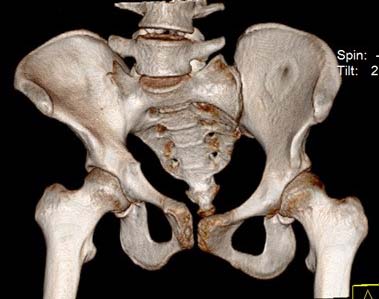

Больная 15 лет. Жалобы: на укорочение правой нижней конечности, хромоту.Анамнез: Со слов болеет с детства, травму отрицает. Ранее за медицинской помощью не обращалась. Последние 2 года отмечает резкое укорочение конечности. Локально: При осмотре отмечается умеренное искривление позвоночника во фронтальной плоскости, умеренная асимметрия лопаток и надплечий. Скошенность таза. Отмечается укорочение правой нижней конечности на 3 см. Движения в тазобедренном и коленном суставах в полном объеме. Нейрососудистых нарушений в периферических отделах нет.

Уважаемый Талгат. Просьба ответить на следующие вопросы: Укорочение у больной анатомическое или функциональное?

Как рентгенологи оценивают состояние крестцово-подвздошных сочленений, не создается ли впечатление о замыкании этого сочленения справа в предшествующие годы, а если это ощущение есть, то что привело к анкилозу этого сочленения. Нет ли по задней поверхности таза в указанной зоне рубца от имевшего место ранее свища?

Наверно целесообразно добавить,что болевого синдрома нет,движения в суставе в полном объёме.Я бы уточнил,что жалобы скорее косметического характера(асимметрия при ходьбе и западение вертельной области справа. Укорочение фигурировало как единственный диагноз в направлении на лечение к нам.Компенсация "укорочения" увеличением высоты каблука обуви не устраняет асимметрию таза и в статике и мало улучшает походку.Вопрос-стоит ли в конкретном случае идти на тройную остеотомию таза и латерализацию вертлужной впадины? Мне представляется,что не стоит.